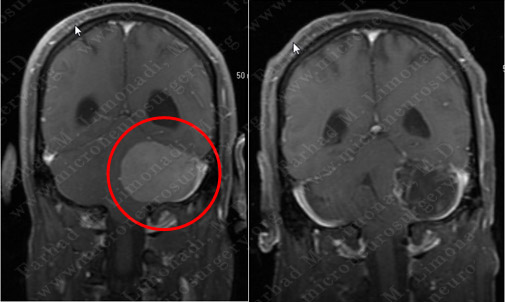

MRI scan of the patient’s brain shows a left extra-axial tumor at the cerebellopontine angle region, resulting in obstructive hydrocephalus with effacement of the fourth ventricle and mass effect on brainstem.

Post-op Imaging

Post-op MRI shows complete resection of the tumor with no injury to surrounding neurovascular structures.